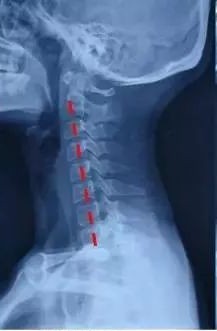

正常的颈椎是一个「C」型结构,颈椎有一个向前凸起,这是它的力学结构基础。这个「C」型的生理弧线保证了颈椎高度的灵活性和稳定性,这也是人体生理和功能的需要。也正是由于这个生理弧度的存在,使得组成颈椎的7块小骨头能够承担整个头颅的重量,并完成各种动作。颈椎曲度是由于颈4至颈5椎间盘前厚后薄形成的,这也是人体生理结构的需要,同时不会让颈椎间盘突出。

我有一个患者,因头晕头痛,容易疲劳,前来就诊,查体后见:颈椎曲度变直,肌肉僵硬,压痛明显,转颈试验(-),臂丛神经牵拉试验(-),霍夫曼征(-)。

经一个月的推拿正骨结合功能锻炼治疗后,头晕头痛症状消失,复查X线片示:颈椎曲度基本恢复。